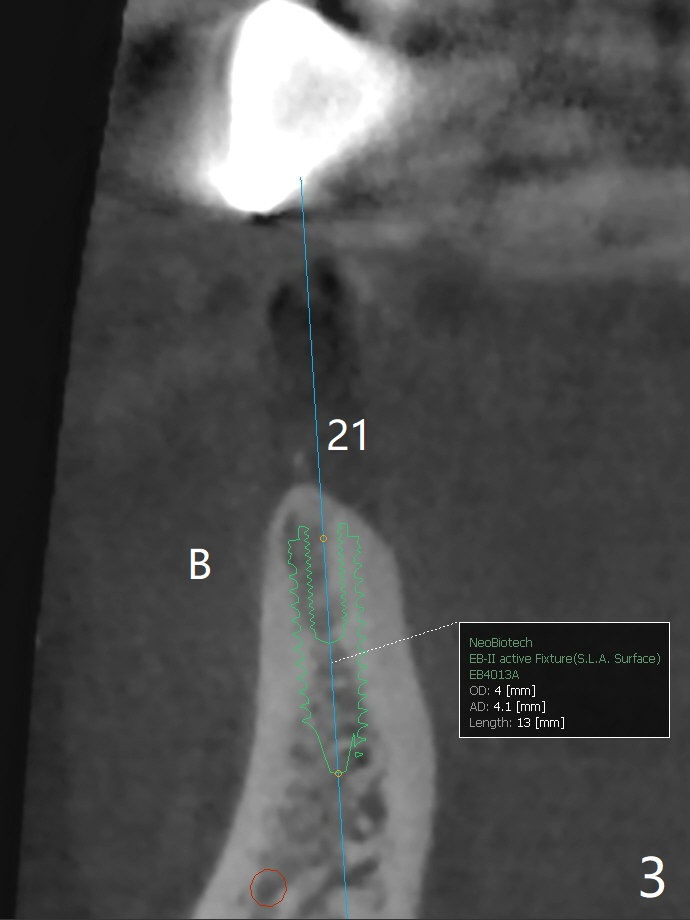

The implants at #11, 14 and 15 are IBS. To reduce the chance of screw loosening, IS guide will be used for better trajectory at #19,21,30. Since the ridge at #21 and 19 is pointed at the top, the implant will be placed deep (Fig.1-4). Bone trimmer will be used prior to pointed drill to avoid drill deflection. Check whether the IS implant driver fits IBS implant well. Try dummy implants first.